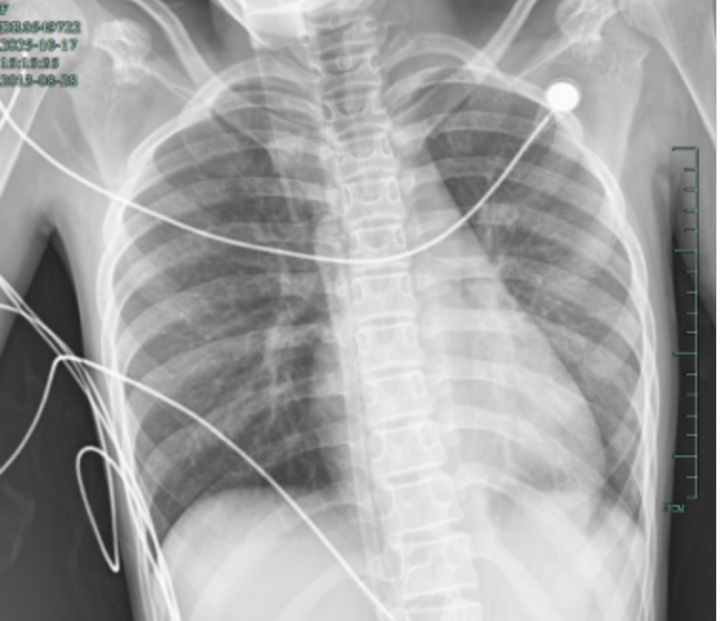

治疗后,“白肺”被吸收,心脏边缘清晰可见

术后第二天,笑笑呼吸困难、胸痛的症状明显好转,病情得到了初步控制,成功从“鬼门关”拉了回来,转回儿科普通病房继续治疗。

值得高兴的是,笑笑的“白肺”基本吸收,恢复如常,没有留下严重的并发症。